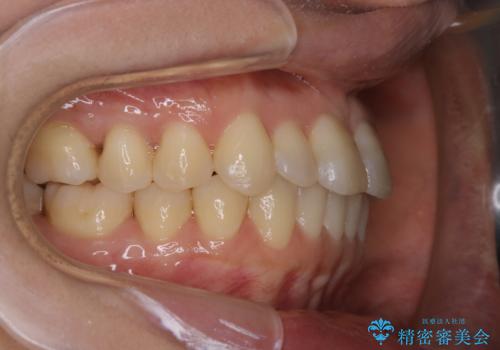

矯正治療とセラミック治療が終了後のPMTC

- 矯正治療とセラミック治療の総合治療が終了したため、クリーニングをしっかりとしてからメンテナンスに入りたいとのことでした。PMTC30分コースを行いました。

矯正治療やセラミックなどによる被せ物の治療終了のタイミングではクリーニングを行い、汚れや着色の除去、歯と歯の間・歯と歯肉との境目などのケアをしっかりすることをおすすめしています。

ご自身での歯ブラシ・セルフケアを行うと同時に、定期的なクリーニング(PMTC)を行うことで、いつまでも健康な歯を保つことができます。